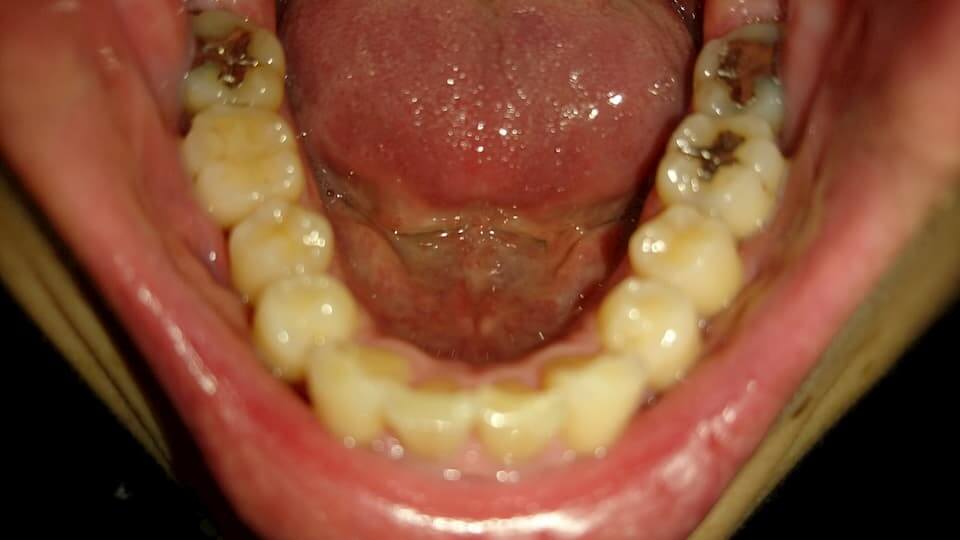

歯の写真